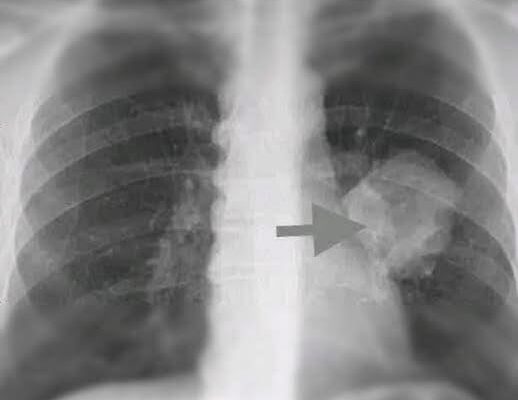

In a startling development that has caught the attention of the international medical community, a team of fully vaccinated researchers has reported the discovery of a previously unidentified type of cancer. Early findings suggest that this disease is spreading silently across multiple continents, posing a challenge to early detection and treatment